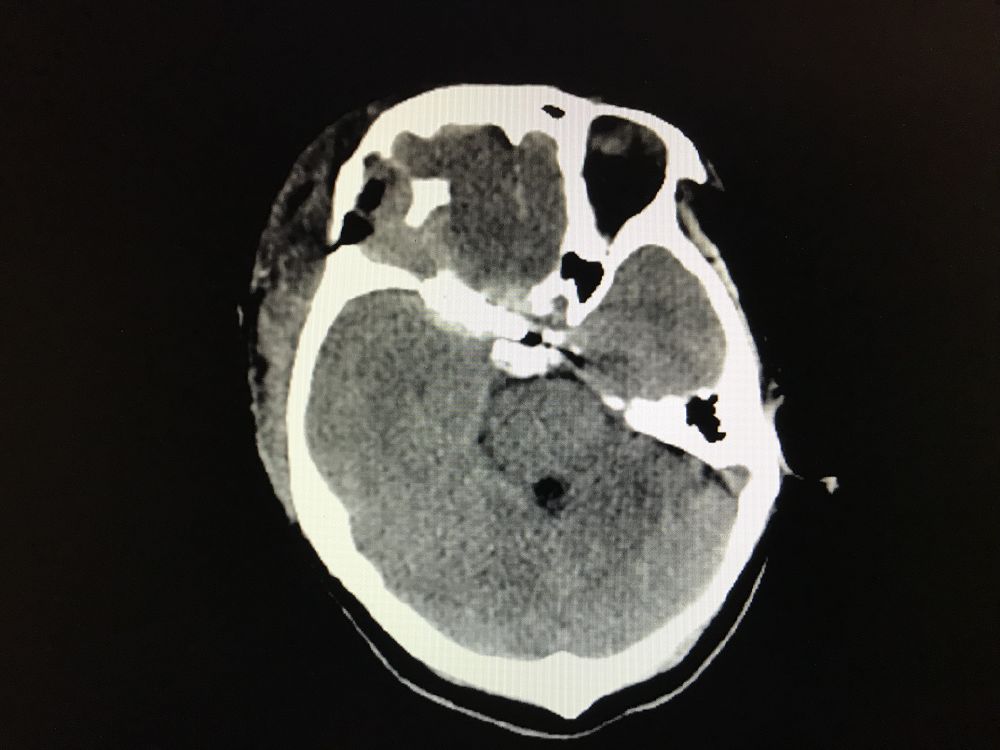

术后患者右眼视力同术前相仿,未出现新发神经功能损害,术后10天出院。

夹闭后复查DSA

术后复查CT